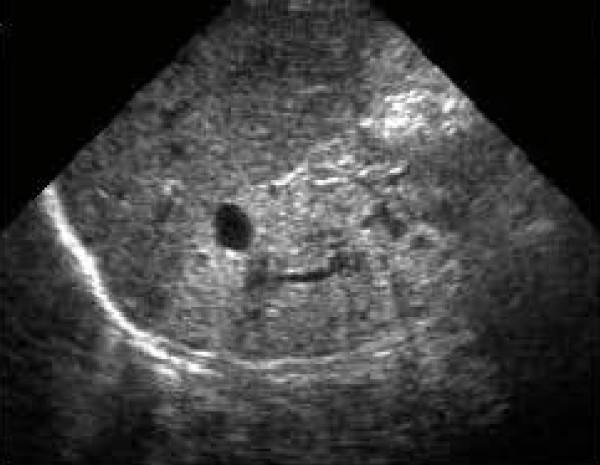

We present the case of a four-year-old Romanian boy who presented to our department with 'febrile seizures'. After an initial evaluation, we diagnosed our patient as having hypertension, severe anemia and end-stage renal disease. He met the major and minor criteria for the diagnosis of Bardet-Biedl syndrome and underwent continuous ambulatory peritoneal dialysis.

我们报告一例4岁罗马尼亚男孩,因“热性惊厥”就诊于我科。初步评估后,我们诊断该患者患有高血压、重度贫血及终末期肾病。他符合巴德-比德尔综合征的主要及次要诊断标准,并接受了持续非卧床腹膜透析。